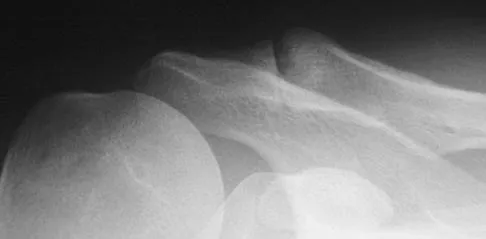

Question 87

Figure 35 shows the radiograph of a 35-year-old weightlifter who has had pain with overhead lifts for the past 7 months. Cortisone injections in the acromioclavicular joint provided only temporary relief. A bone scan reveals increased activity of the acromioclavicular joint. Treatment should now consist of

Explanation